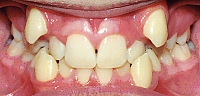

Zahnfehlstellung Engstand

Engstand nennt sich der Platzmangel der Zähne bei

einem zu kleinen Kiefer [6]. Kiefer werden zu klein

-- durch zu wenig Wachstumsreiz, wenn das Kind nicht

gestillt wird, sondern immer die Flasche bekommt [2]

-- durch Verlust der Milchzähne im frühen Kindesalter

durch Flaschenkaries, so dass die Milchzähne ihre

Rolle als "Platzhalter"nicht mehr wahrnehmen können

[5].

Engstand der Zähne, eine Frontalansicht |

Engstand bei einem Unterkiefer, eine Sicht